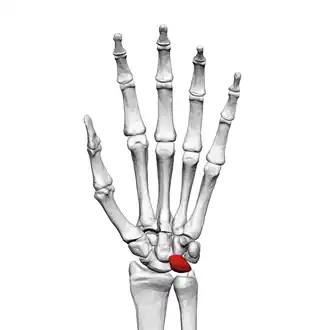

Left hand anterior view (palmar view). Lunate bone shown in red.

The lunate bone (semilunar bone) is a carpal bone in the human hand. It is distinguished by its deep concavity and crescentic outline. It is situated in the center of the proximal row carpal bones, which lie between the ulna and radius and the hand. The lunate carpal bone is situated between the lateral scaphoid bone and medial triquetral bone.

The lunate is a crescent-shaped carpal bone found within the hand. The lunate is found within the proximal row of carpal bones. Proximally, it abuts the radius. Laterally, it articulates with the scaphoid bone, medially with the triquetral bone, and distally with the capitate bone. The lunate also articulates on its distal and medial surface with the hamate bone.[2]: 708 [3]

The proximal surface of the lunate bone is smooth and convex, articulating with the radius. The lateral surface is flat and narrow, with a crescentic facet for articulation with the scaphoid bone. The medial surface possesses a smooth and quadrilateral facet for articulation with the triquetral bone. The palmar surface is rough, as is the dorsal surface. The dorsal surface is broad and rounded. The distal surface of the bone is deep and concave.[4]